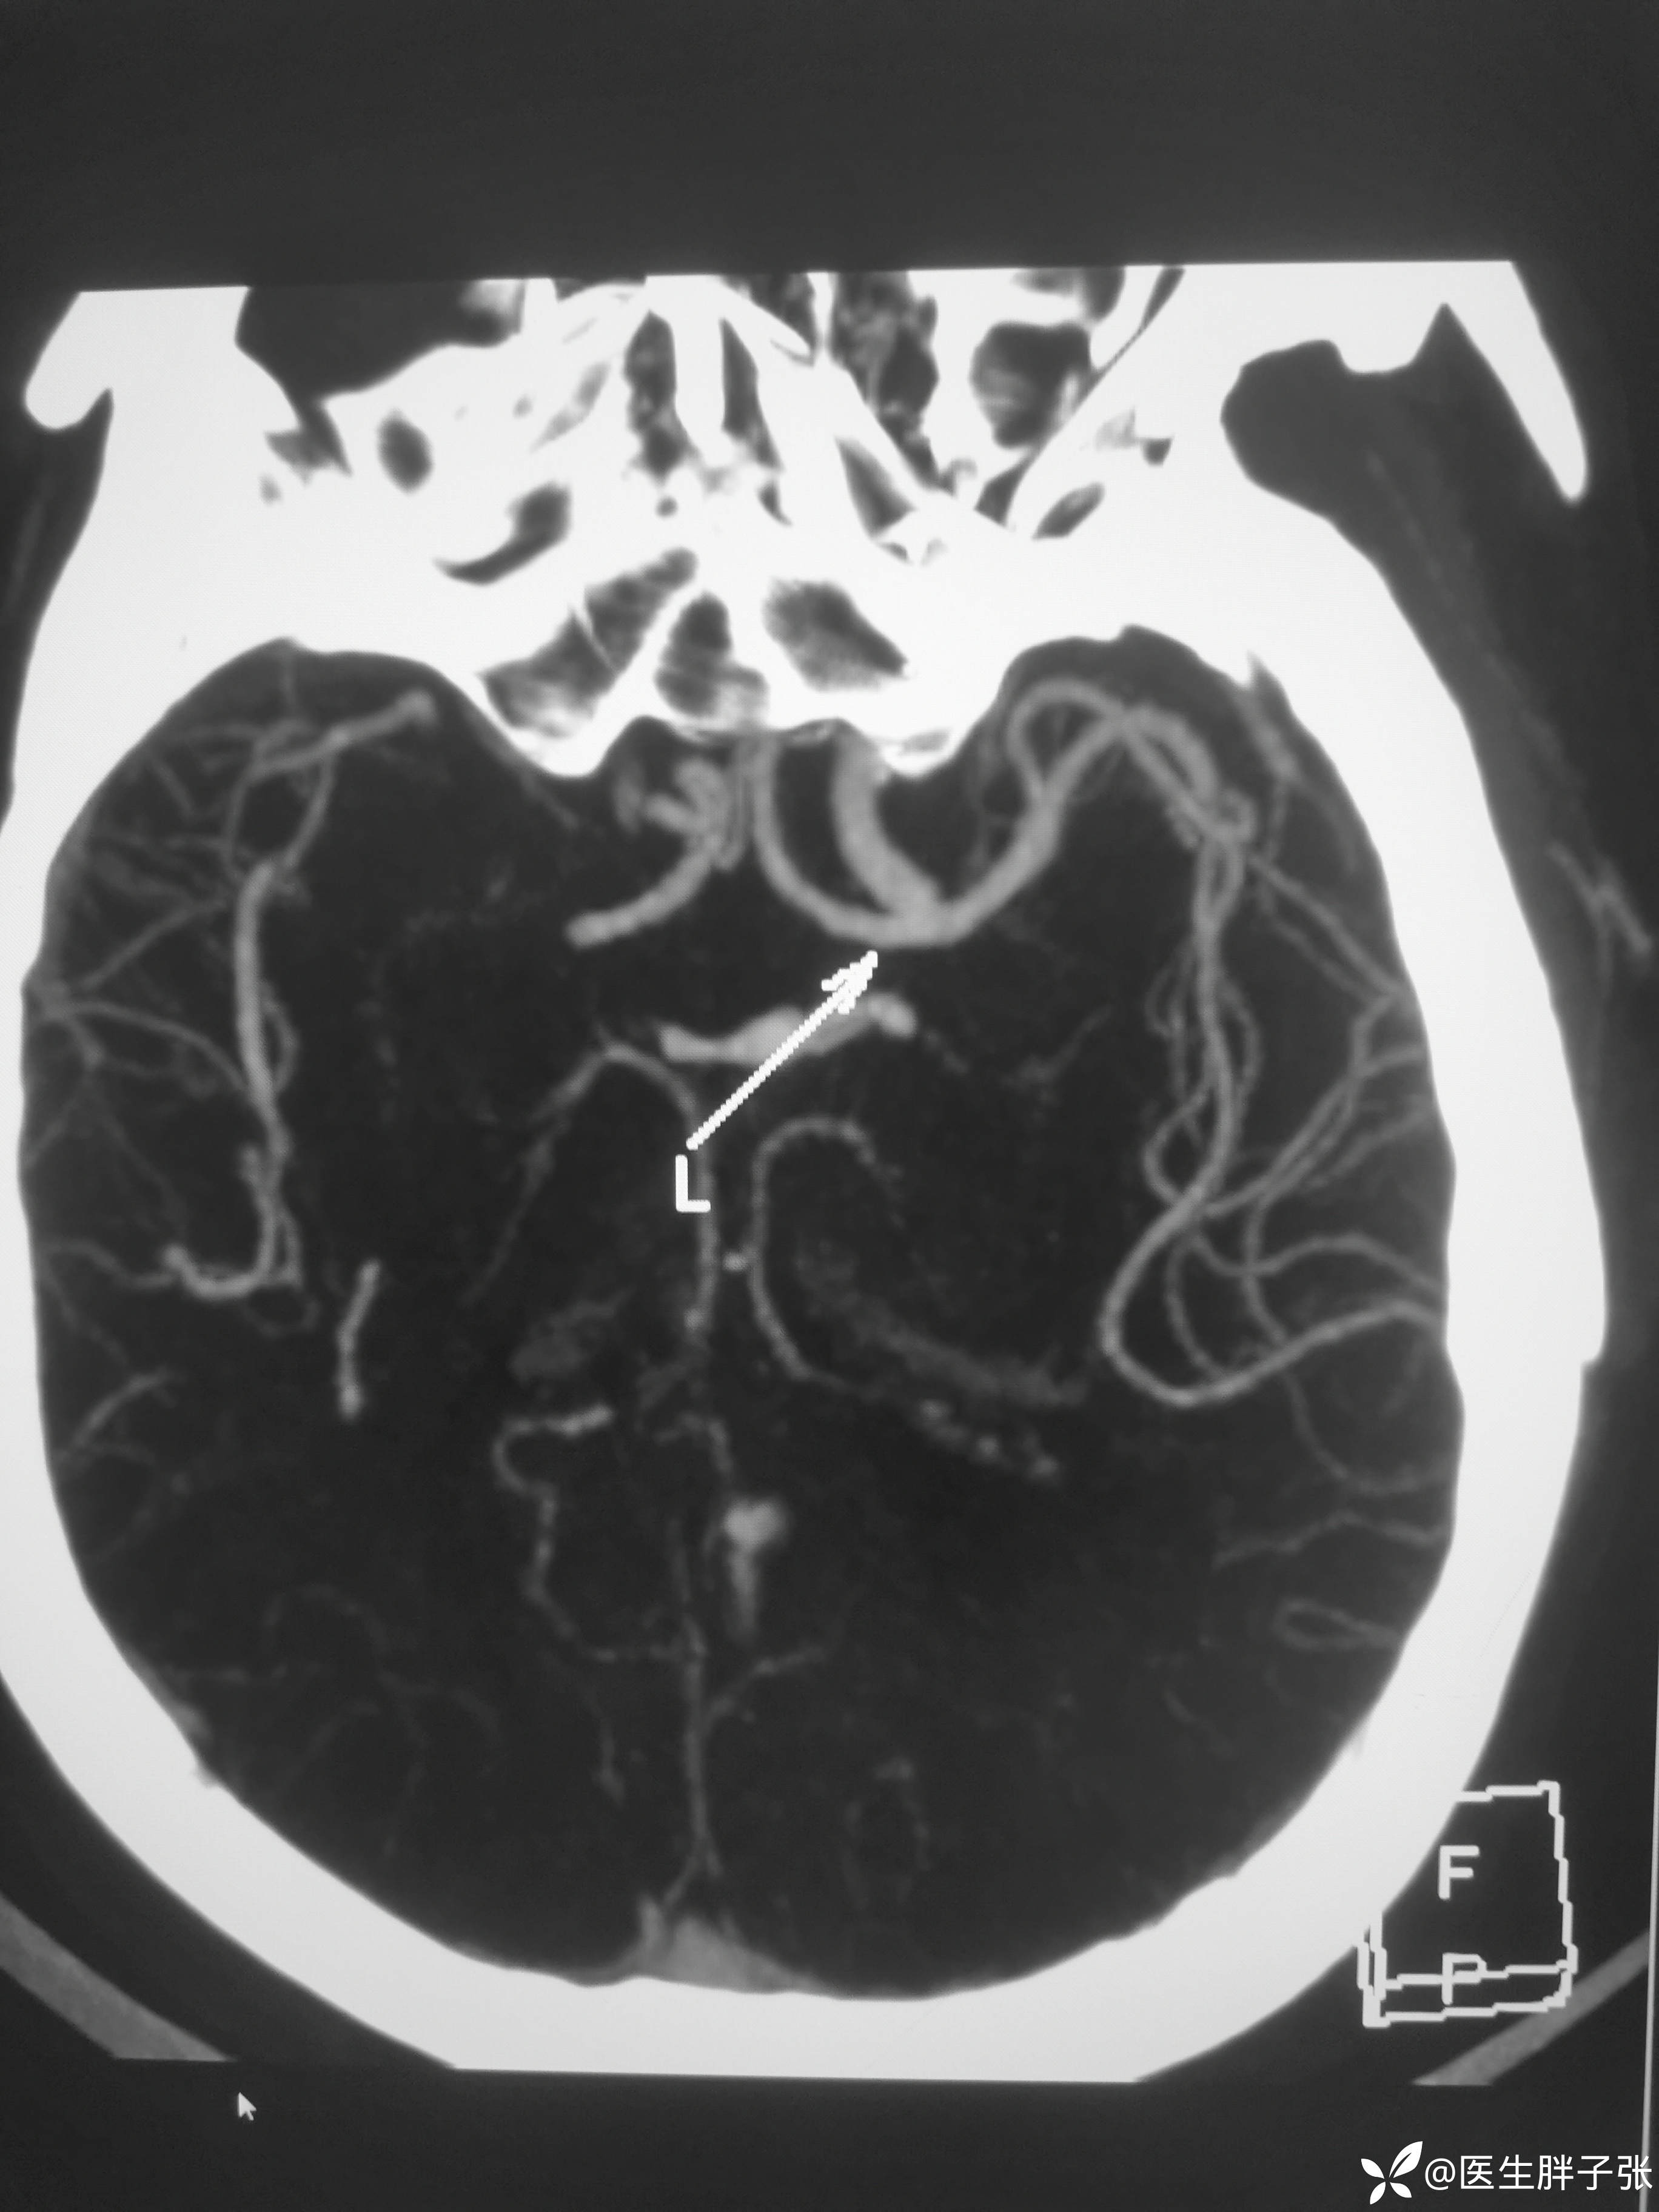

颅脑MR提示左侧枕叶、基底节区、顶叶、双侧额叶新发梗死。

头颈部CTA